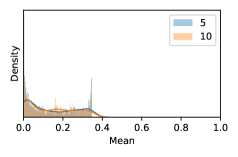

To model how different classifiers will respond to a given input , we assume that the prediction from classifier is sampled from a beta distribution that is characterized by two parameters by and . We further assume that is fixed to the same constant value for all ’s. Under this assumption, each input can be described by ( can be calculated since is fixed), easing further analysis. The Severity Level (SL) of the case represented by image can be characterized by the parameter . The larger the value of , the more severe the case of is. When and are close, the case is ambiguous as the distribution shifts towards being symmetric (i.e. signifying much disagreement among classifiers) rather than being one-sided (i.e. consensus among classifiers that is negative or positive). We provide a set of examples in Figure 2 and also Figure S.8 in the supplementary materials showing how the beta distribution can be used to capture diverse predictions given by an ensemble learner.

In contrast, the MC-dropout method showed the worst overall performance among the three, as it can be seen from the high ratios of SL0 examples among the uncertain negatives in Figure 4. The histograms in Figure 2 provides another perspective to look into the phenomenon, where a decent proportion of MC-dropout model’s predictions on SL0 inputs entailed low confidence (far from 0 or 1), which from another angle explained why MC-dropout was less specific in terms of lower FNP; many no-DR inputs (i.e. SL0) were erroneously assigned high uncertainty by MC-dropout models.

As discussed in Section 5.1 and Section 5.3 in the main paper, the mean metric and the stacking ensemble will have better performance in the precision (specificity) on the ambiguous data. Here, more detailed results are shown in Figures S.3 & S.6 and Table S.1. Figures S.3 & S.4 show the histograms of the uncertainty score for Kaggle-DR and Messidor-2 datasets that are the in-distribution (i.d.) dataset in our experiment and FigureS.5 & S.6 show the histograms for ImageNet and CIFAR-10 datasets, which is the o.o.d. datasets in our experiment. Each group of histograms contains results from the three evaluated ensemble methods (stacking ensemble, MC-dropout and TTA) and the three uncertainty metrics (mean, var and kl). Additional detailed results not displayed in Figure 4 can be found in Table S.1, which shows the proportion of the data of different SLs varies across different . For comparison, we also included in Table S.1 the results from single learners, and the proportions of data of different SLs (before any selection was made).